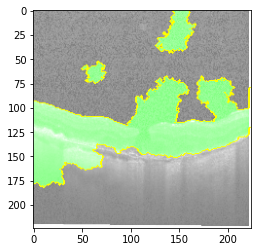

Fig 6, 7, 8 and 9 depicts the visualization of correct predictions by our proposed CNN model where fig 6 is class CNV, fig 8 is class DME, fig 7 is DRUSEN and finally, fig 9 is NORMAL. Here the first photo in every class is the original image. The LIME map of our suggested model’s prediction is shown in image B whereas in image C the positive region is highlighted in specific sections on the original image. For Image D we have increased the number of features from 5 to 10 thus more regions have been predicted as the positive region which is highlighted in green. After increasing the features from 5 to 10, some of the regions are predicted wrongly. The red regions represent the output of incorrect prediction. The following image represents the Grad-CAM heatmap highlighting the regions with our model’s prediction.